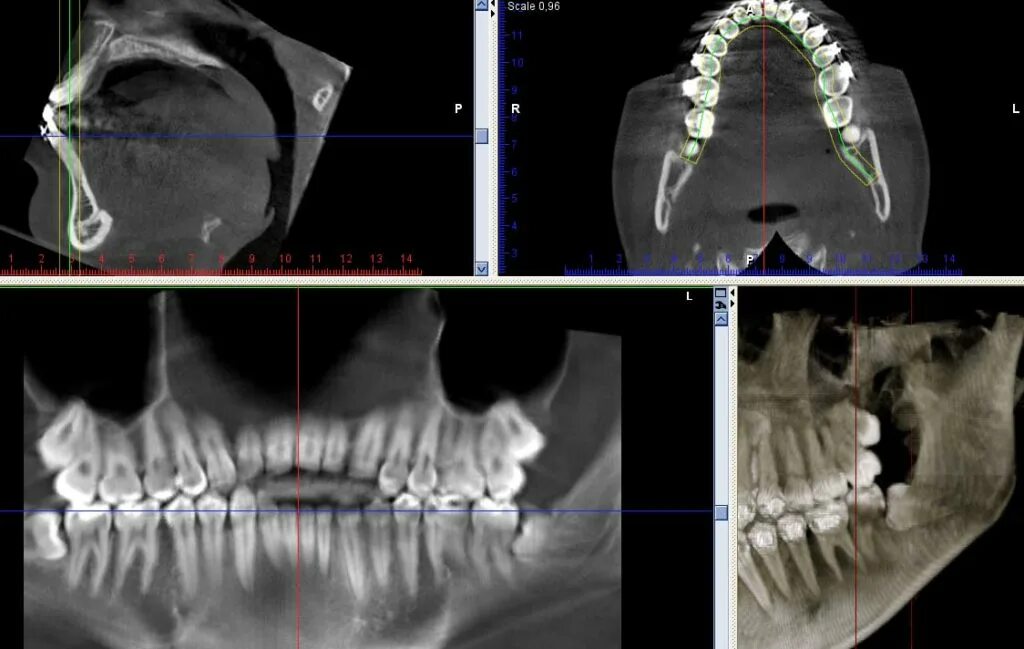

Зуб дистопирован